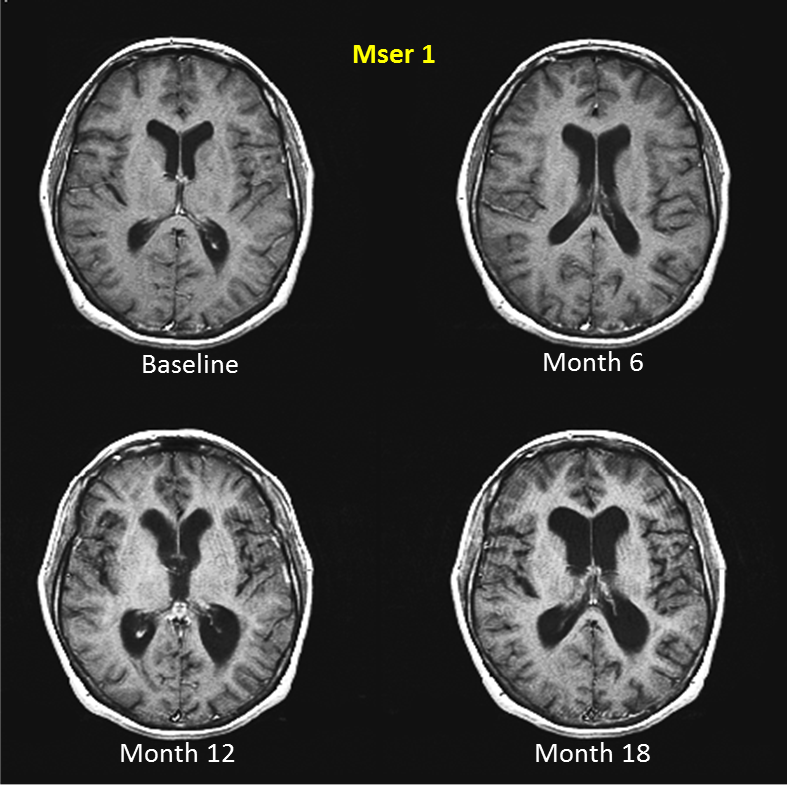

"As a follow-up to yesterday's post on brain atrophy; please study the MRIs above. These MRIs are from two MSers I met when I did my PhD from 1993 to 1996; they were participating in a phase 2 clinical trial of a biological therapy that targeted CD4 T-cells (anti-CD4 therapy). Unfortunately, the anti-CD4 trial was negative. This trial still questions the role that CD4 cells play in the pathogenesis of MS; well at least in my mind. Most immunologists still believe MS is driven by CD4 T cells; but that is another story."

"What the serial MRIs on these MSers show is the extraordinary amount of brain atrophy that can occur over an 18 month period - look at the black spaces in the centre of the brain, the ventricles, and see how they enlarge over 18 months. Also look at the black spaces on the surface of the brain, the sulci, and see how they open up over 18 months. This brain atrophy is partly due to loss of axons and neurones and is unequivocally linked to disability progression and cognitive impairment. This is why there is increasing emphasis on drugs that can prevent or at least slow the rate of brain atrophy down."

"Preventing atrophy completely is unlikely to happen as brain atrophy occurs as part of normal ageing; from the age of 35 our brains shrink - mine included. The aim therefore would be shift the brain atrophy rate in MSers to that which occurs in normal ageing. Can we do this? Not yet, although several DMTs are showing promise in this area. This is why we are keen to explore attitudes to incorporating brain atrophy into clinical practice."